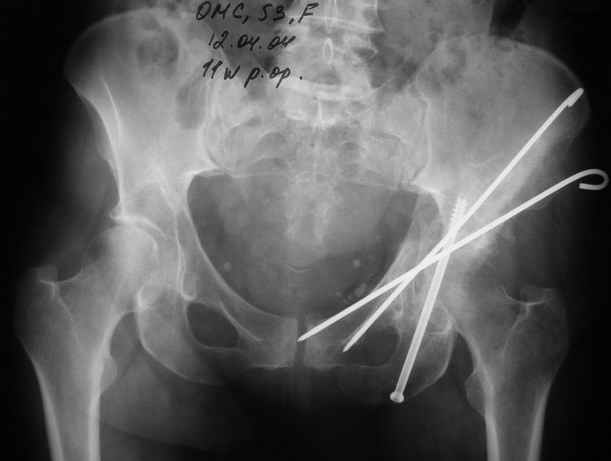

12.04.04